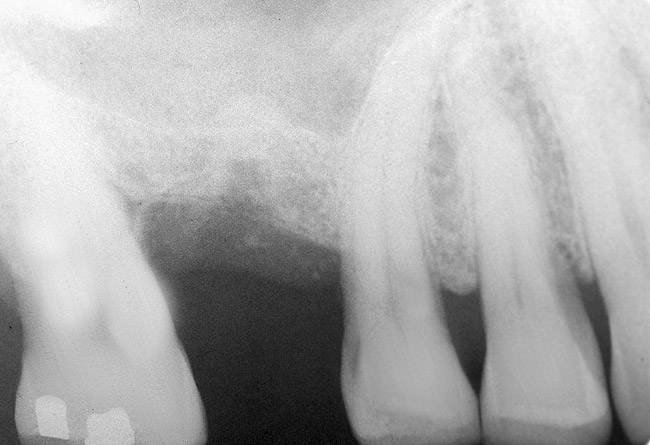

The 2-mm twist drill is used to create an osteotomy 1 mm short of the subantral floor. If any resistance is detected prior to reaching the 3-mm depth, drill penetration must be stopped, because the subantral cortical bone has possibly been reached. Any uncontrolled "push" would penetrate the bone and likely perforate the sinus membrane. A guide pin is then inserted and a radiograph taken to determine if drill penetration has terminated within 1 mm of the subantral floor (Figure 2). If the radiograph indicates that more than 1 mm of bone is present subantrally, the twist drill is used again to penetrate within 1 mm of the sinus floor. Alternately, an osteotomy tip for a piezosurgery unit can be used for this purpose. The final depth of penetration should be verified with another periapical film.

Figure 2  After drilling to a depth of 3 mm with a 2.1-mm twist drill, the guide pin was placed and a radiograph was taken to ascertain if the drill stopped within 1 mm of the subantral floor.

Figure 2

Figure 9: After the extraction, a 2.1-mm twist drill was used to drill within 1 mm of the subantral floor. A guide pin was placed and a radiograph was taken to ascertain if the drill stopped within 1 mm of the subantral floor.

Figure 9